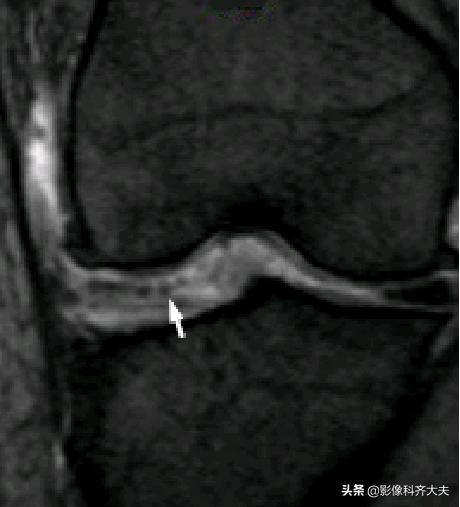

Ⅲ级:半月板内高信号达一个或两个关节面。Ⅲ级A型:线形高信号达关节面。Ⅲ级B型:不规则高信号达关节面。表示一个确定撕裂。可为部分性或全层撕裂。常伴有症状。病理上可见纤维软骨断裂伴或不伴肉眼可见的表面蔓延 。

水平方向撕裂